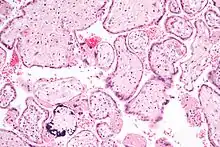

Placental mammals, such as humans, have a chorioallantoic placenta that forms from the chorion and allantois. In humans, the placenta averages 22 cm (9 inch) in length and 2–2.5 cm (0.8–1 inch) in thickness, with the center being the thickest, and the edges being the thinnest. It typically weighs approximately 500 grams (just over 1 lb). It has a dark reddish-blue or crimson color. It connects to the fetus by an umbilical cord of approximately 55–60 cm (22–24 inch) in length, which contains two umbilical arteries and one umbilical vein.[6] The umbilical cord inserts into the chorionic plate (has an eccentric attachment). Vessels branch out over the surface of the placenta and further divide to form a network covered by a thin layer of cells. This results in the formation of villous tree structures. On the maternal side, these villous tree structures are grouped into lobules called cotyledons. In humans, the placenta usually has a disc shape, but size varies vastly between different mammalian species.[7]